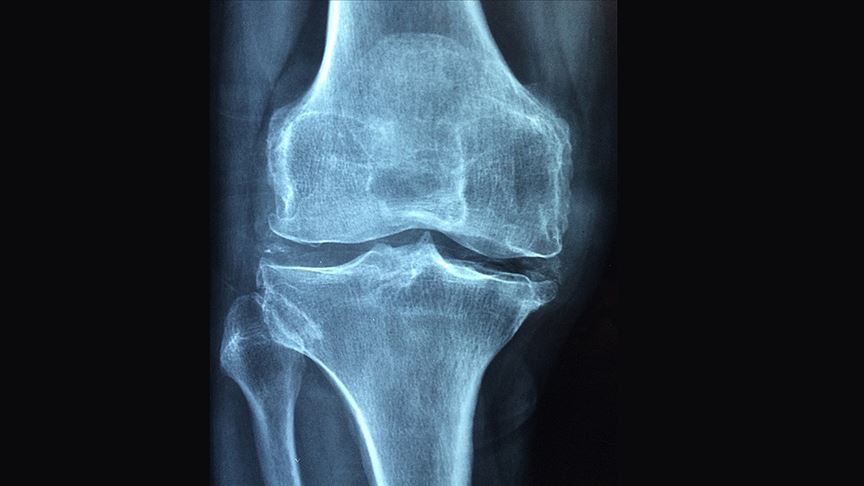

Dünyanın En Yaygın Eklem Hastalığı

Osteoartrit, dünya genelinde yaklaşık 600 milyon insanı etkiliyor. The Lancet'te yayımlanan veriler, bu sayının 2050'ye kadar bir milyara yaklaşabileceğini gösteriyor. Daha uzun yaşam süresi, kilo artışı ve masa başı yaşam bu artışın başlıca nedenleri arasında yer alıyor.

Kıkırdak Hareketle Besleniyor

Eklem kıkırdağı, kan damarları olmayan özel bir dokudur. Besinini hareket sayesinde alır. Yürürken ya da çömelirken kıkırdak sıkışır, içindeki sıvıyı boşaltır ve gevşediğinde taze besinleri emer. Her adım, eklemin kendi kendini onarmasına katkı sağlar.

Bugün hastalığın tüm eklemi etkilediği biliniyor. Eklem sıvısı, kemik, bağlar, çevredeki kaslar ve sinir sistemi bu sürecin parçası. Bu yüzden tek başına ağrı kesici ya da enjeksiyonlarla kalıcı çözüm sağlanamıyor.